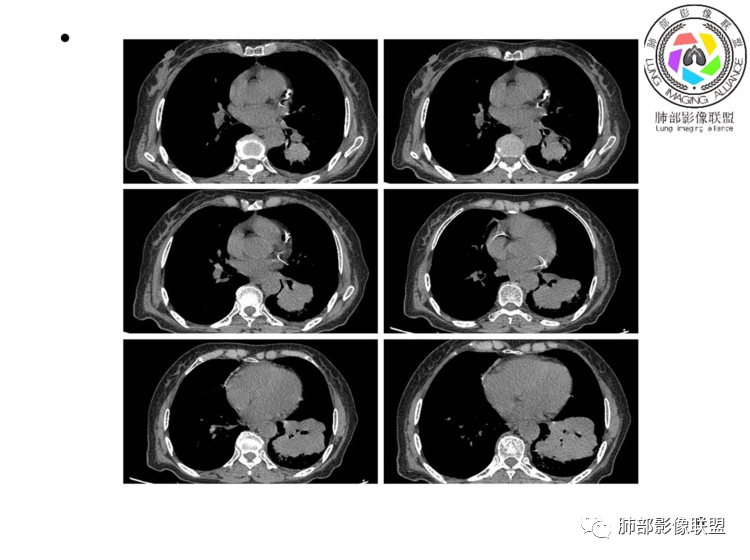

左肺下叶团块,边缘膨隆分叶,支气管部分阻塞、部分进入扩张,密度不均,延迟强化,血管走行正常,病灶与左侧膈肌分界不清。考虑恶性肿瘤:1淋巴瘤;2肉瘤样癌。

老年女性,上腹部疼痛为主诉,CT所示左肺下叶肿块,左肺下叶支气管变窄,局部阻塞,病灶可见分叶,内见僵硬稍扩张的支气管,增强扫描病灶中度强化,内见血管造影征,首先考虑恶性病变,腺癌和淋巴瘤需要考虑,转移瘤待排除。

老年女性,左肺下叶软组织肿块,密度较均匀,边缘膨隆分叶,临近支气管截断,肿块内可见支气管穿行,与膈肌分界不清,增强后动脉期轻度均匀强化,静脉期呈渐进性强化,欠均匀,内血管走形如常,可见血管漂浮,整体感觉病灶偏软,考虑淋巴瘤可能大,鉴别腺癌。

老年女性,上腹部疼痛一周,肿标CA125升高。胸部CT:左肺下叶巨大肿块,分叶,密度不均,与左膈肌分界不清,内见枯枝征,部分支气管进入后截断,增强中度延迟强化,见血管漂浮征。胃壁不均匀增厚。考虑:恶性肿瘤病变伴阻塞性炎症,淋巴瘤?腺癌转移?鉴别TB、隔离等。

老年女性,左下肺大肿块、深分叶,考虑恶性肿瘤。纵隔肺门淋巴结无明显肿大,不支持小细胞癌;支气管进入后截断、肿块破坏力不强,不支持鳞癌,内部血管走行自然,不怎么支持腺癌,支持淋巴瘤;肉瘤似乎内部很少见支气管。

左下肺肿物,有分叶及血管飘浮征,定性恶性,无胸膜牵拉及毛刺,提示收缩力差,可排除腺癌。女性,肿块内坏死不明显(鳞烂心)不首选鳞癌。老年女性,血管飘浮,特别是膈肌受累首选淋巴瘤

考虑淋巴瘤!鉴别腺癌 首先看病灶恶性征象多,深分叶支气管截断,支气管感觉是受压闭塞,肺动脉显示良好,血管漂浮征!这么大肿瘤如果是鳞癌不可能没有坏死!腺鳞癌同样如此,肉瘤样癌同理,类癌、不典型类癌明显强化,而这例轻度延迟性比较均匀强化,淋巴瘤感觉是符合 特别是MALT

弥漫性大B细胞淋巴瘤